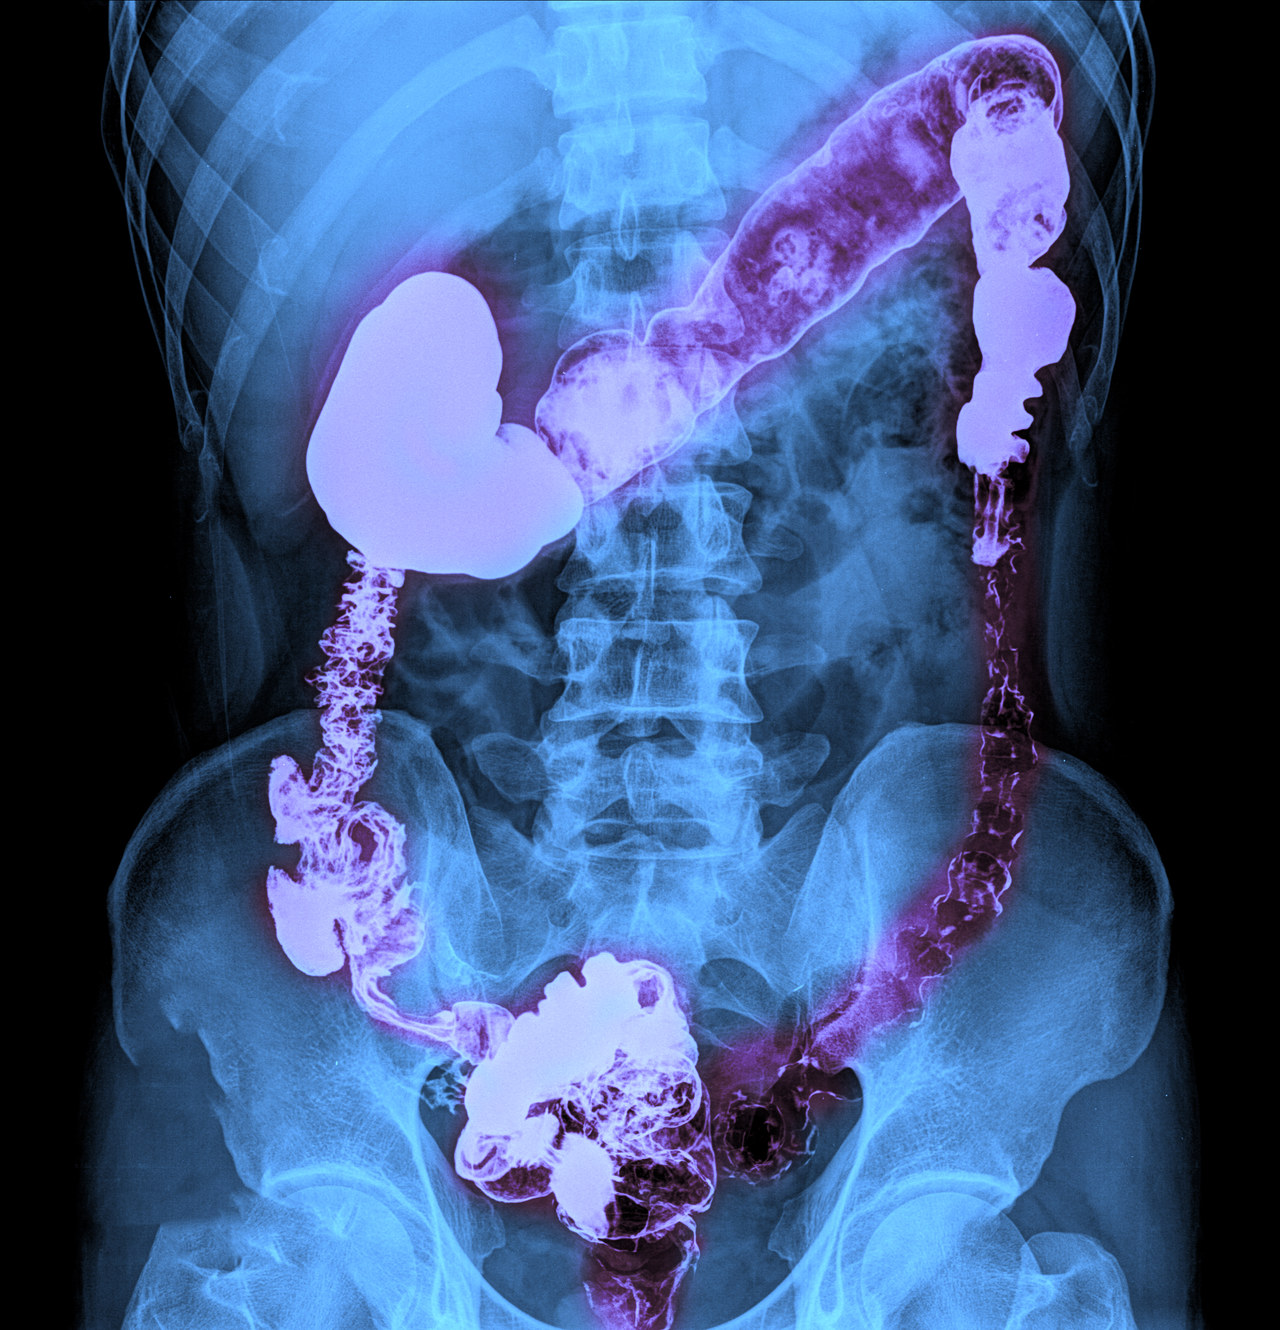

4. X线检查

气钡双重造影**:可用于诊断结直肠癌,但不能用于分期。该检查可以帮助发现结肠内的充盈缺损、狭窄等异常改变。